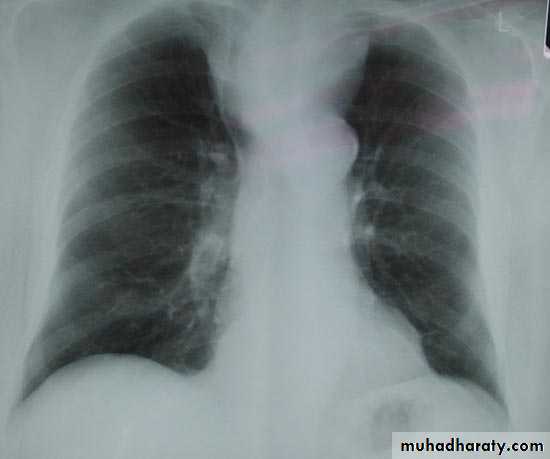

The pleura :

• Pleural effusion : collection of fluid within the pleural space. This can be further divided into Transudate , exudate, according to protein content .Other type of fluid collection within pleural space are

• Chest x-rays are the most commonly used examination to assess for presence of a pleural effusion, however it should be noted that on a routine erect frontal chest x-ray as much as 200-500 ml of fluid is

• required before it becomes evident .

blunting of the costophrenic angle

blunting of the cardiophrenic angle

fluid within the horizontal or oblique fissures

eventually a meniscus will be seen, on frontal films seen laterally and gently sloping medially

with large volume effusions, mediastinal shift occurs away from the effusion

Pleura effusion signs

Obliteration of costo-pherinic anglesMeniscus sign